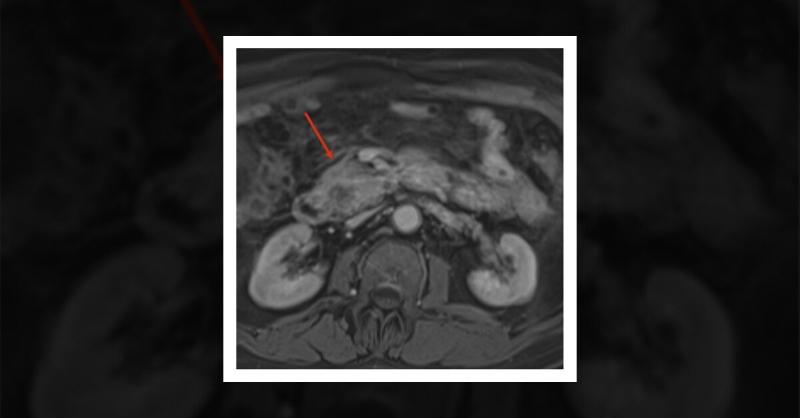

Myeloid Sarcoma Mimicking Pancreatic Mass

A 70-year-old man with recently diagnosed leukemia cutis of the eyelid presented with one week of epigastric abdominal pain and jaundice. Physical examination revealed a slightly distended, non-tender abdomen with scleral icterus and jaundice. Biochemical data showed elevated levels of total and direct bilirubin, aspartate aminotransferase, alanine